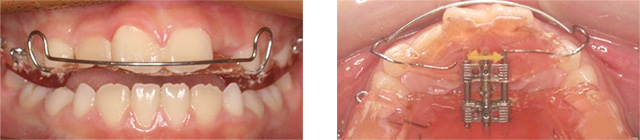

공간부족으로 인하여 치아가 제대로 나오는 못한 2급 부정교합 환자입니다. 고운미소에서 악궁을 넓혀주는 급속구개확장술 (RPE)를 적용하여 비발치 교정을 진행하였습니다.

급속구개확장술 (RPE) 장치로 빠르게 상악이 확장되었습니다. 넓어진 공간으로 치아가 이동이 되어 발치를 하지 않고 가지런하게 치아교정이 되었습니다.